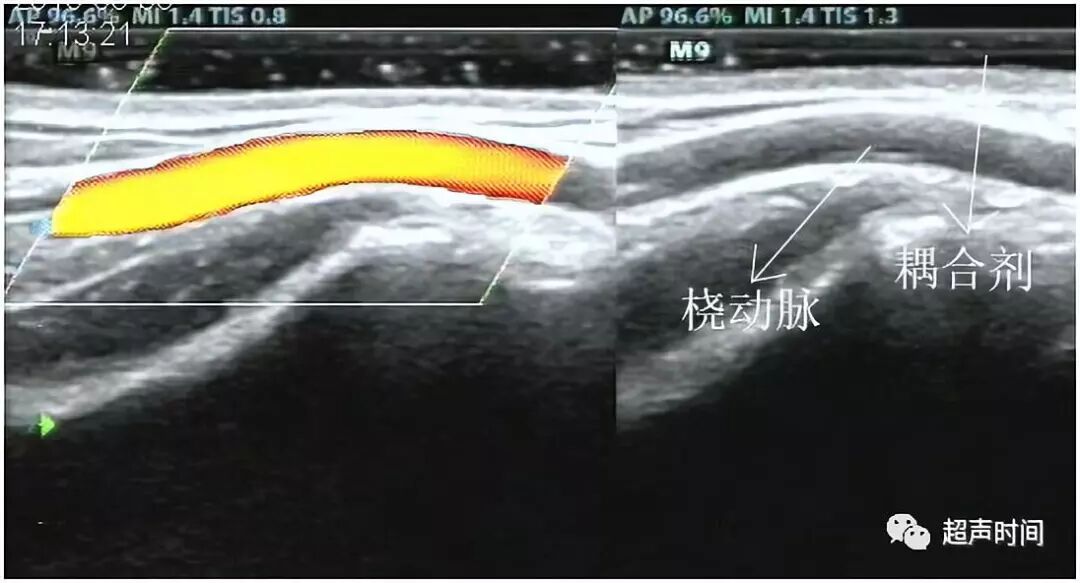

动脉:肱动脉、桡动脉位于较深层,肌肉与肌肉之间,有对应静脉伴行。桡动脉在肘窝位置及腕部最为表浅(图 2)。

图 2

动静脉内径:经血管纵向和横断面测量(图 3 和图 4),测量时应尽量与血管走行保持平行或垂直,避免夸大或缩小管腔内径。应在报告中应说明测量的大致位置,或用标记笔在体表标记。

图 3 和图 4

测量浅表静脉(如贵要静脉、头静脉)时,患者应保持静息状态,在其体表多涂抹耦合剂,探头悬空不能压迫静脉,否则影响其内径评估。